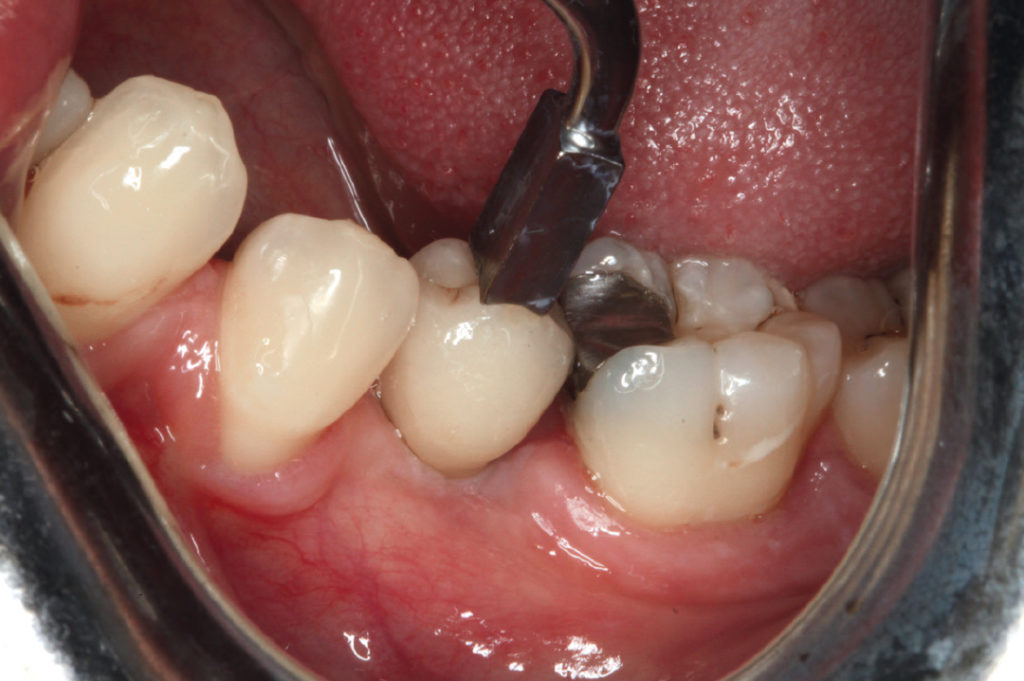

Full thickness flap to expose the bone in the region of tooth #35

Use of round bur to mark the cortical bone

Implant site preparation for the placement of a Leone 6.5 short implant

Leone 6.5 short implant in place